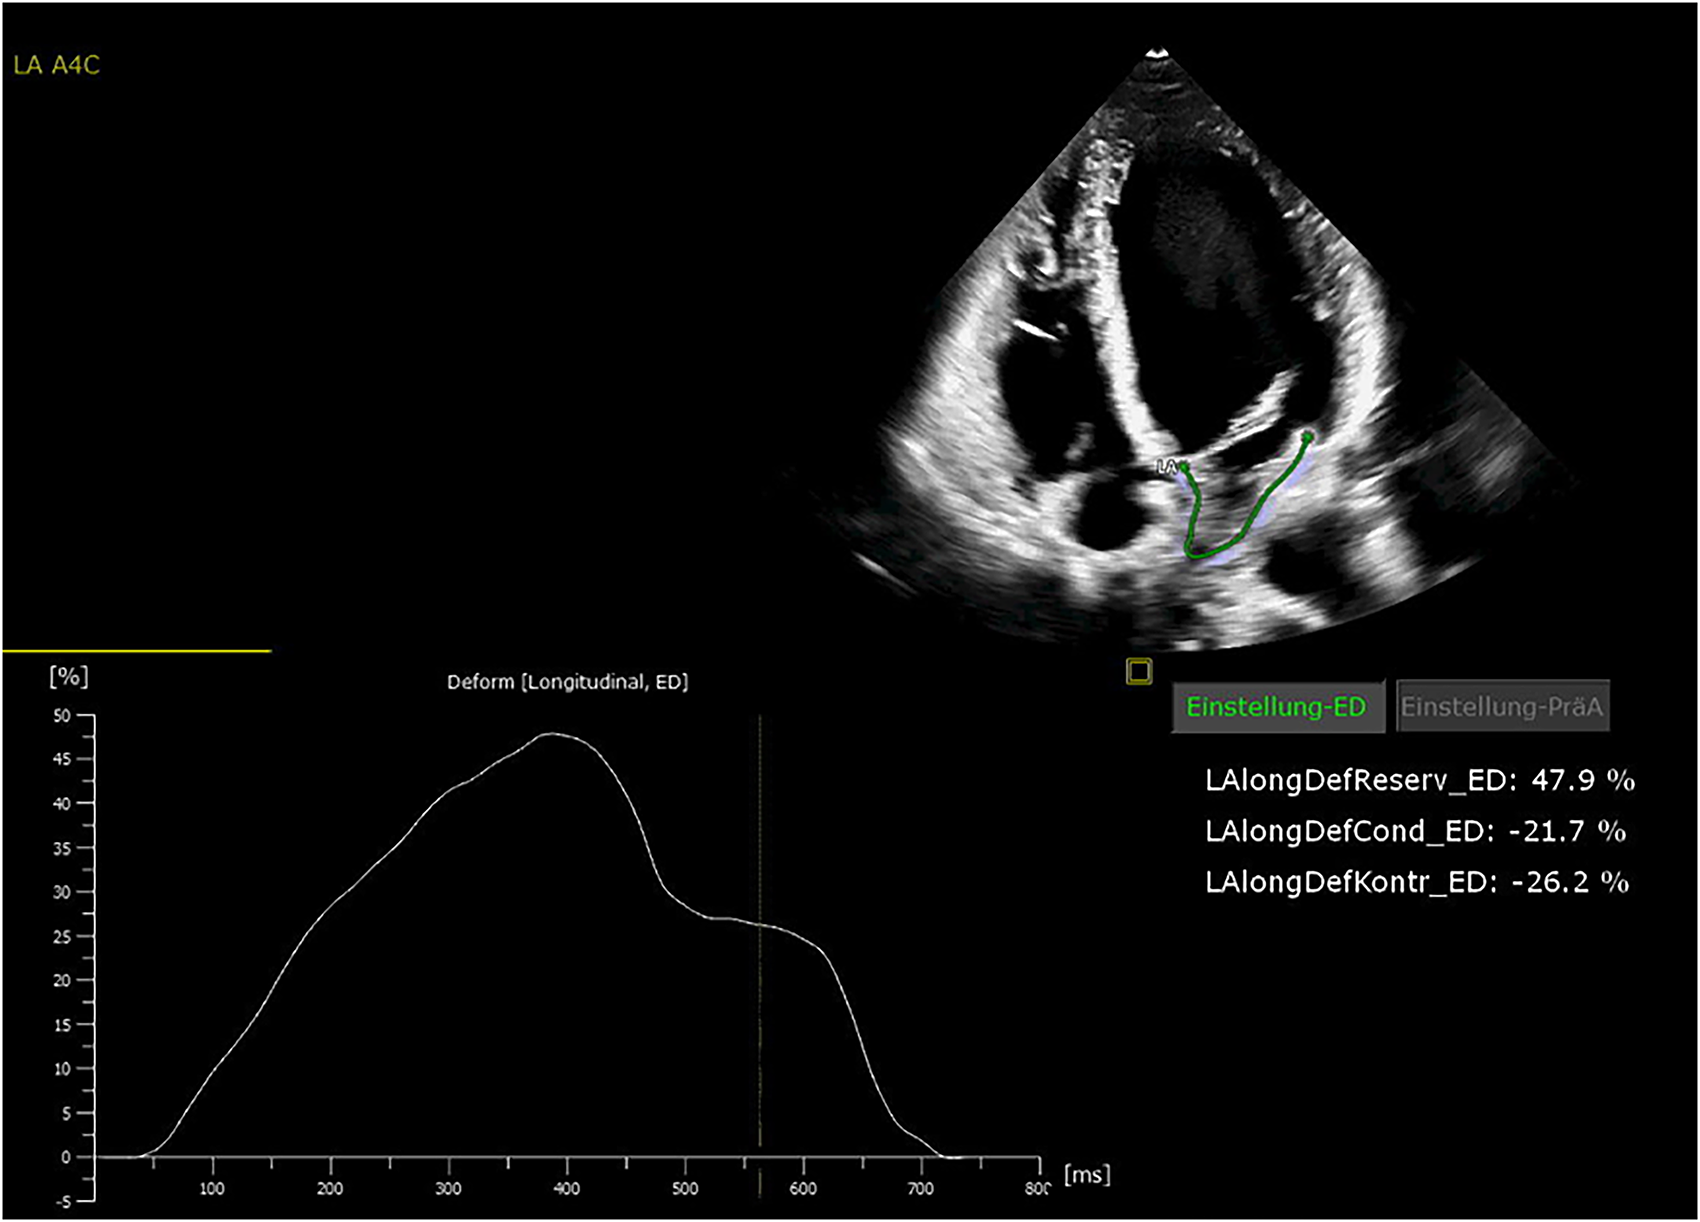

All patients were in AF at the time of preoperative transthoracic echocardiography. The patients were examined by transthoracic echocardiography. After manual tracing of the LA endocardial border, the software Cardiac Performance Analysis (IMAGE-COM, TOMTEC-ARENA, TOMTEC Imaging System GmbH, Unterschleissheim, Germany) automatically tracked the myocardium throughout the cardiac cycle (Figures 2, 3). LA reservoir strain was presented. The same measurements were performed to assess LV strain measurements. The additional echocardiography included an assessment of left ventricular ejection fraction (LVEF), diastolic function, LV hypertrophy, and measurement of LA and left ventricular diameters and volumes. The measurements were according to the current recommendations (21), which are also applicable to strain measurements (22).

Figure 2

Echocardiography showing normal left atrial (LA) strain values.